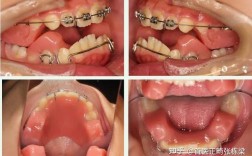

牙齿矫正过程中,部分人可能会感觉牙齿“变长”,这一现象需要从牙齿矫正的生物学原理、牙齿结构变化以及视觉错觉等多角度综合分析,牙齿矫正并不会让牙齿本身的解剖结构(如牙冠长度)发生实质性增长,所谓的“变长”更多是临床牙冠长度(牙龈缘至牙尖的距离)的变化,或由牙齿移动、牙龈位置调整等共同作用产生的视觉效果。

牙齿矫正的核心是通过矫治器(如传统托槽矫正器、隐形矫正器等)对牙齿施加持续、轻柔的力,引导牙齿在牙槽骨内缓慢移动,这一过程依赖牙槽骨的改建:在压力侧,牙槽骨发生吸收(为牙齿移动提供空间);在张力侧,牙槽骨则发生沉积(支撑牙齿移动),牙齿本身(包括牙釉质、牙本质、牙髓等硬组织)的结构不会因矫正而发生改变,牙冠的解剖长度(即牙齿从牙龈最深处到牙尖的固有长度)是固定的。

牙齿矫正中,牙齿移动往往会带动牙龈组织一同调整位置,对于原本存在牙龈覆盖过多(如“牙龈微笑”)、牙齿萌出不足的情况,矫正过程中牙齿被牵引至理想位置后,牙龈缘会随之向根方移动,暴露更多牙体组织,导致“临床牙冠长度”增加,即视觉上的“牙齿变长”,这种变化属于正常的生理性调整,目的是让牙齿与牙龈形成更协调的轮廓(如理想的“牙龈乳头高度”和“游离龈边缘”)。

相反,若矫正前存在牙龈萎缩(如牙周炎导致的牙根暴露),矫正过程中牙齿移动可能暂时加剧牙龈退缩,使牙根暴露更多,也会让人感觉“牙齿变长”,但这属于异常情况,需提前干预牙周问题。

部分矫正者的牙齿存在倾斜、扭转等问题(如门牙过度唇倾),牙冠实际长度未变,但因倾斜角度导致牙龈缘至牙尖的“投影长度”较短,矫正后,牙齿被直立至正常位置,牙冠与牙长轴的角度趋于垂直,原本被“压缩”的视觉长度得以释放,从而感觉牙齿“变长”,唇倾的门牙矫正后,牙冠中1/3显露量增加,整体视觉上更修长。

传统矫正中,托槽粘接于牙面,可能暂时覆盖部分牙体组织,拆除托槽后,原本被遮挡的牙体暴露,会让人感觉牙齿“变长”,矫正初期牙齿移动可能出现轻微“伸长”(如打开咬合时后牙被压低,前牙被动伸长),但这种伸长是暂时的,随着咬合关系调整会恢复正常。